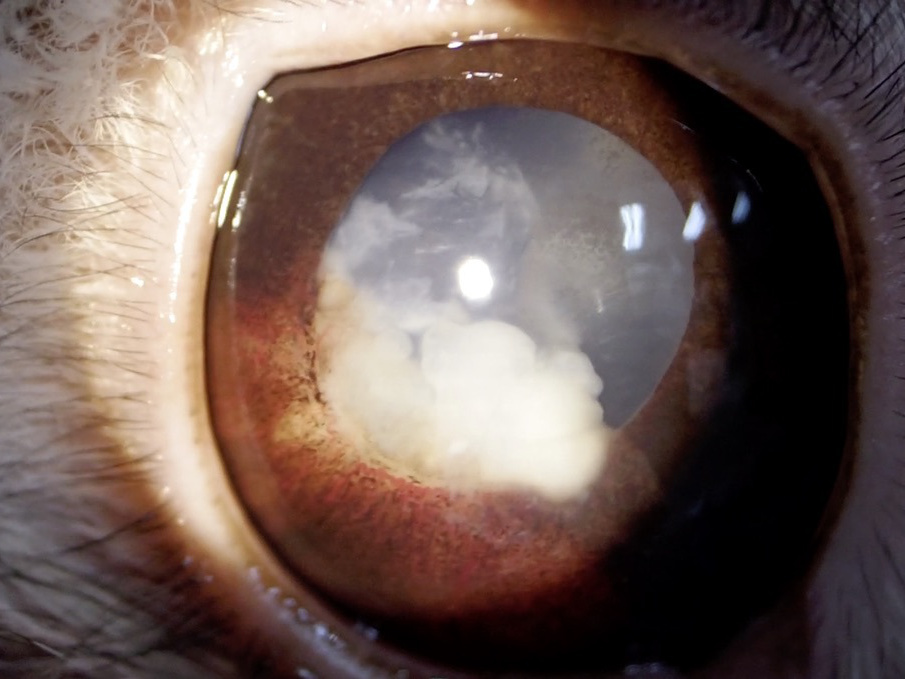

成熟白内障

水晶体の混濁が全体にわたり、視覚がない状態になります。